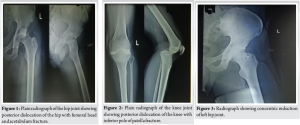

A 28-year-old gentleman with no known comorbidities was involved in a high-velocity road traffic accident (2-wheeler vs. 2-wheeler). The patient presented to the emergency department of our hospital 2 h after the time of incident with painful deformities over his left hip and left knee. There was no history of head injury, ear, nose, and throat bleed, abdominal pain, breathing difficulty. On examination, he was hemodynamically stable with no evidence of intracranial hemorrhage, intra-abdominal bleeding, or hemopneumothorax. His left hip was flexed, adducted, and internally rotated and left knee was in 30°–40° flexion with posterior sag, restricted hip and knee movements. Dorsalis pedis and posterior tibial pulses were well palpable and equal to that of the contralateral limb. There were no signs of neurological deficits with the presence of ankle dorsiflexion and plantar flexion without any sensory loss. As a first line of investigation, X-ray of left hip and X-ray of the knee joint were done which revealed posterior dislocation of the left hip with posterior acetabular wall fracture (Fig. 1) and posterior dislocation of the knee with inferior pole of patella fracture (Fig. 2).